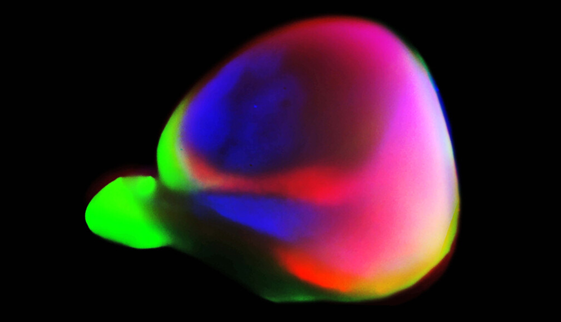

☞ 생쥐, 마카크원숭이, 인간의 뇌 피질(brain's cortex) 차이(참고 3)

a. 시바타 등(참고 1)은 생쥐, 마카크원숭이, 인간의 뇌(실물 크기를 반영하지 않았다)를 비교했다. 그 결과, 3종(種)의 동물 공히 발생기 동안 레티노산(retinoic acid) 분자의 농도가 뇌 피질의 앞에서 뒤로 갈수록 점차 감소하며, 전반적인 농도는 인간이 가장 높고 생쥐가 가장 낮은 것으로 나타났다. 인간의 전전두피질(PFC: prefrontal cortex)은 마카크원숭이와 생쥐에 비해 확장되었고, 다른 뇌 구조인 시상과의 상호연결(reciprocal connection) 개수가 생쥐의 PFC보다 많은 것으로 나타났다(연결은 그림에 표시되지 않았다).